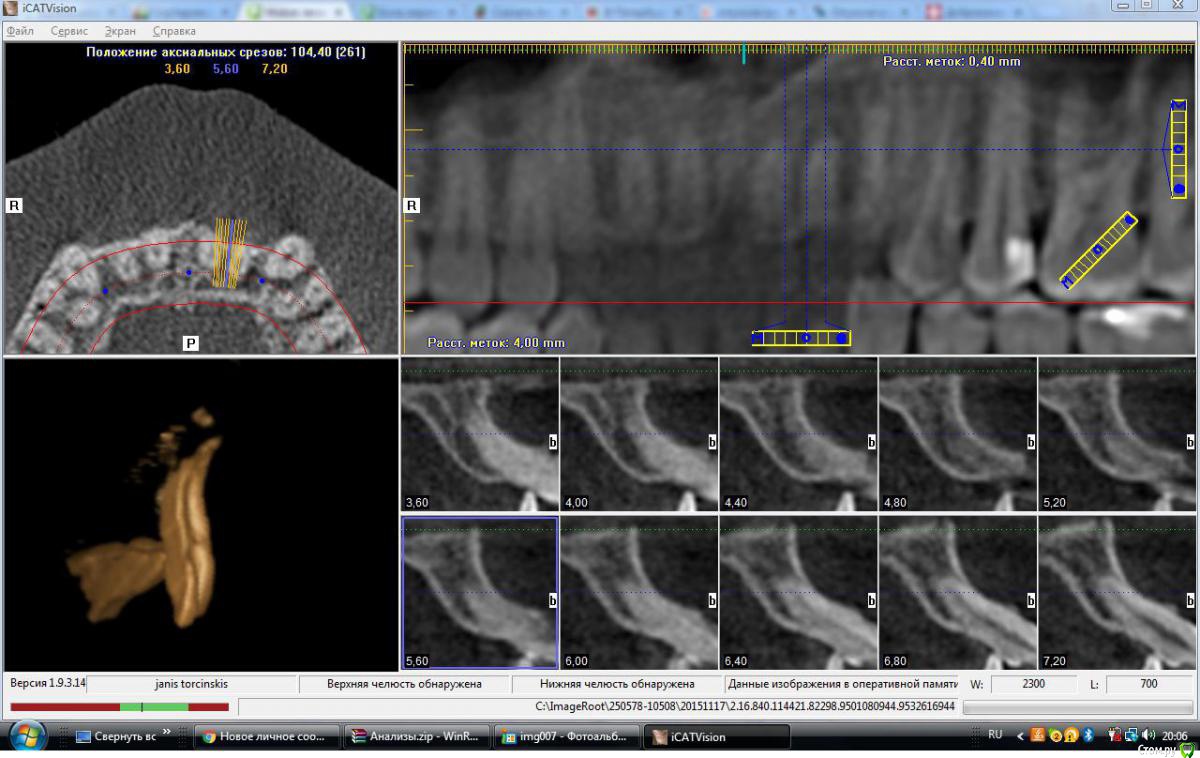

janis1 Опубликовано 17 ноября, 2015 Автор Поделиться Опубликовано 17 ноября, 2015 (изменено) Здравствуйте ещё раз. Вот ссылка на полный iso образ диска c томографией, вместе с программой просмотра iCATVision (380мб).iCATVision Data.iso Вот ссылка на архив папки с файлами, файлы с расширением dcm. (105мб).2.16.840.114421.82298.9501080944.9532616944.ZIP Надеюсь вас такие размеры не испугают Заранее всем спасибо за ваше потраченное время!!! Изменено 17 ноября, 2015 пользователем janis1 Ссылка на комментарий

kozloff Опубликовано 18 ноября, 2015 Поделиться Опубликовано 18 ноября, 2015 Подозреваю пульпит зуба 25И к лору не помешает сходить, есть отек слизистой. Гайморита нет. Ссылка на комментарий

Jurai Опубликовано 22 ноября, 2015 Поделиться Опубликовано 22 ноября, 2015 Есть проблема во фронтальном участке верхней челюсти: общая убыль костной ткани, ячеистая структура кости. смещение зубов так, что корни изогнулись, это значит, что либо резорбция (рассасывание) либо очень длительное уже идет воздействие. Могу подозревать новооборазование в этом участке.Вам нужна консультация челюстно-лицевого хирурга-онколога. 1 Ссылка на комментарий

kozloff Опубликовано 29 ноября, 2015 Поделиться Опубликовано 29 ноября, 2015 Не могут ли подобные симптомы говорить о каком либо бактериальном заражении либо воспалительном процессе? Нет. Рекомендую начать с малого. Обратите внимание на зубы 25, 26. Там возможен кариес/пульпит. Обратитесь на очную консультацию для этого к терапевту-стоматологу. Далее консультация ортодонта. 2 Ссылка на комментарий